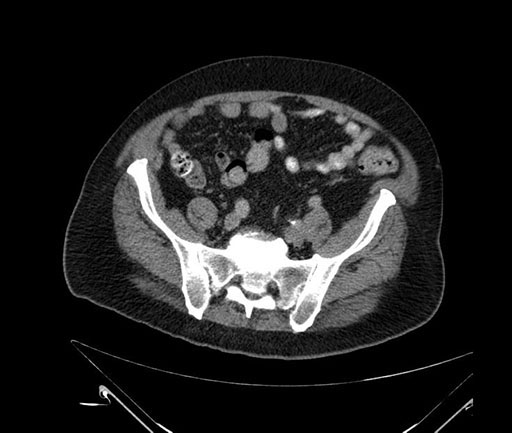

Whipple (pancreaticoduodenectomy) [case 7]

Imaging Analysis

Look through the patient's CT scan to identify any areas of concern for the necessary procedure.

Axial - 3 months prior